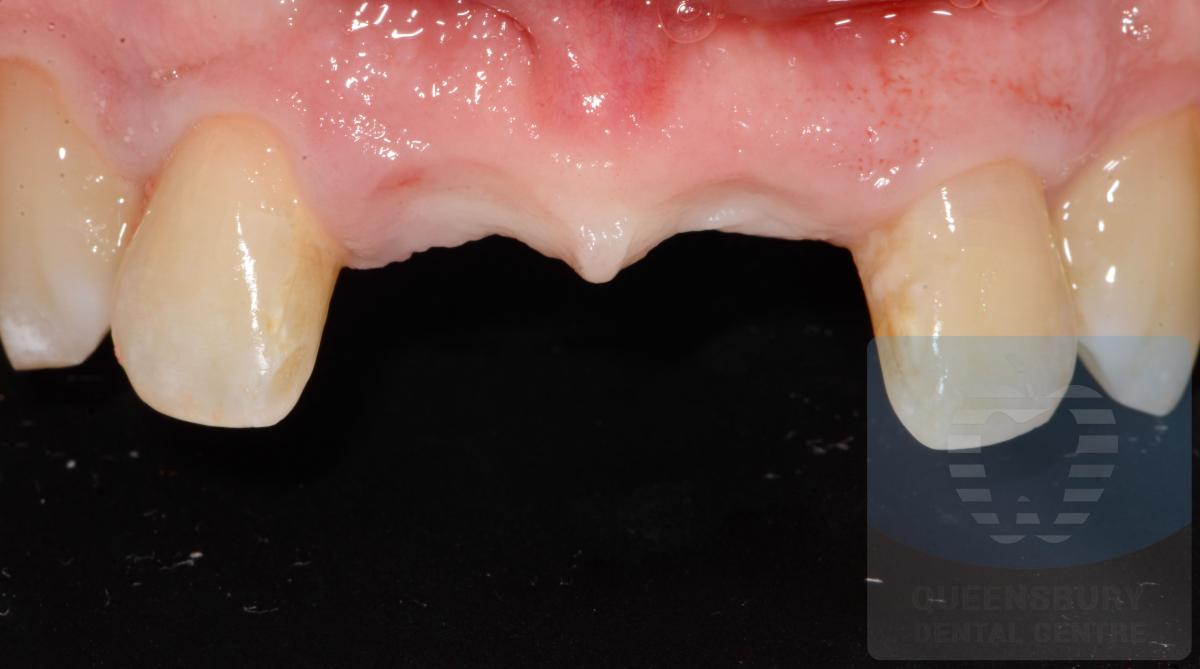

Missing teeth and loose dentures make many people avoid social settings because they are too self-conscious about their appearance. Current dental procedures, however, replace everything from a single missing tooth to a completely missing arch. Ask your dentist or dental specialist about the different dental options that are available to you. Don’t let another day go by without taking this important first step to restoring your confidence and your smile!